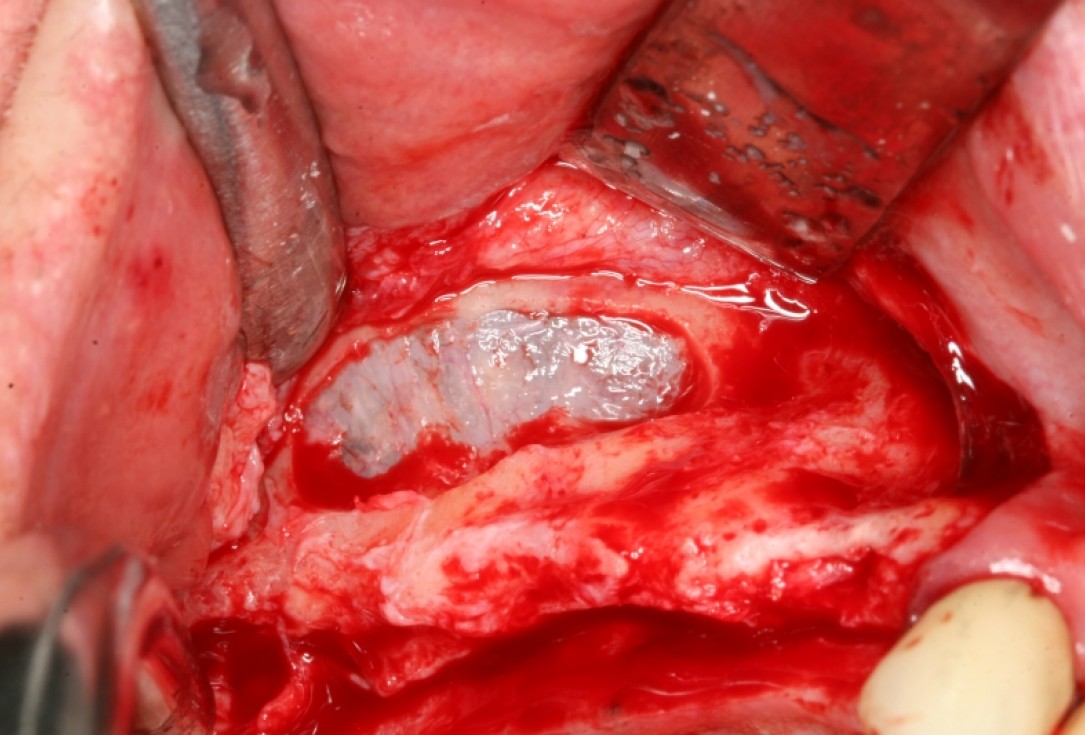

03/13 - Surgical presentation of the ridge with mobilization of the sinus mucosa through a lateral window

Sinus lift with simultaneous bone splitting & implantation - Dr. F. Kistler